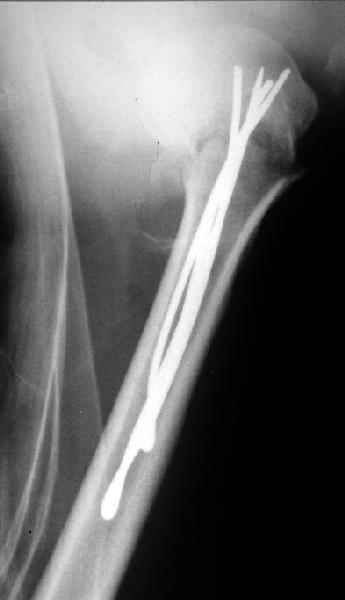

Женя, а как ты водишь спицы, в смысле, как делаешь входное отверстие, и как в него проводишь V-спицу? А то о дна из спиц, та, у которой не дошла до головки одна палочка буквы V, как-то выглядит на рентгенограмме, как будто или через очень большое отверстие введена, или каждая половинка через отдельные отверстия.

В чем ты видишь причину вторичного смещения?

Мне кажется, проблема в том, что не все концы спиц зашли в головку, и зашедшие - недостаточно далеко прошли.

С комментариями абсолютно согласен.

Спицы провожу по передней и задней поверхностям плечевой кости через 4,5 мм отверстия на разных уровнях.

Идеей презентации случая была демонстрация важности постоп Рг - хотя казалось бы все было сделано под флюороскопическим контролем и интраоперационно подозрений на нестабильность не возникло, а такая вот

неожиданность...

V-спица проводится через 4,5 мм отверстие. Видимо, из-за разной длины вторая половина спицы *пролетела* мимо отверстия, что и привело к вторичному смещению костных фрагментов.